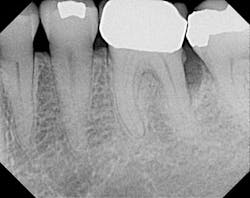

X-ray before.